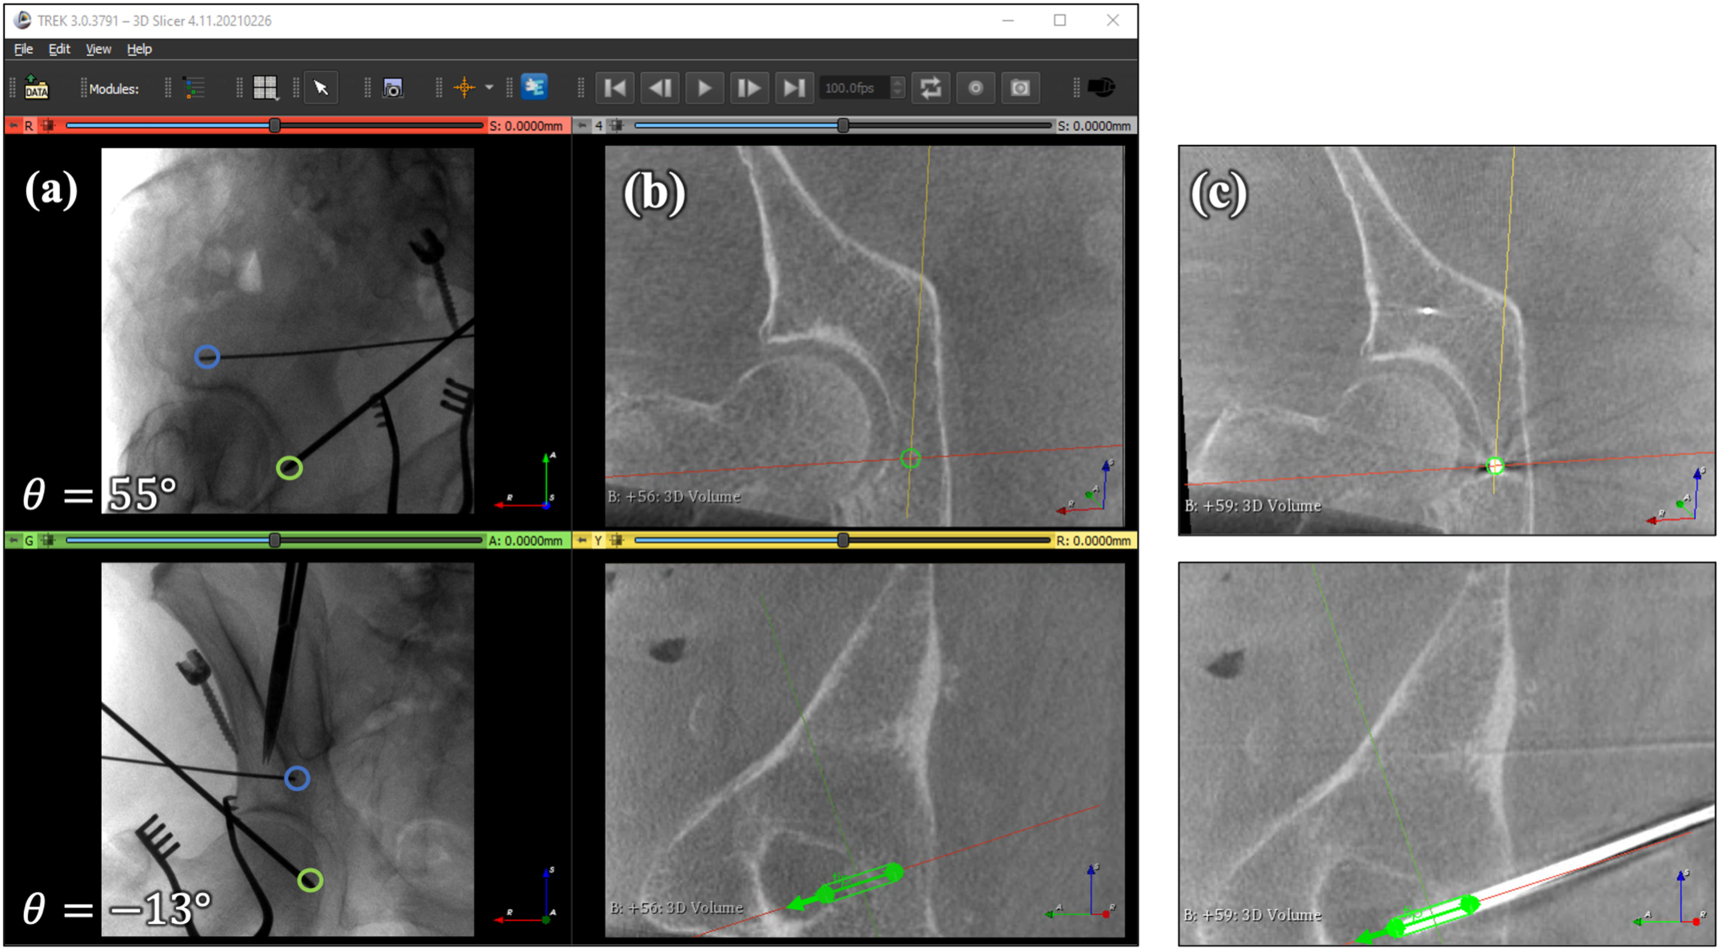

Surgical navigation for guidewire placement from intraoperative

Surgical navigation for guidewire placement from intraoperative Guidewire Orthopedic Surgery A guide wire is a thin, flexible, medical wire inserted into the body. Hip surface replacement arthroplasty (sra) can be an alternative for total hip. surgical guidewires are commonly used in placing fixation implants to stabilize fractures. Here we explore the various types of medical guidewires available and their uses. A variety of medical interventions use them, from heart. Guidewire Orthopedic Surgery.

Surgical navigation for guidewire placement from intraoperative Guidewire Orthopedic Surgery surgical guidewires are commonly used in placing fixation implants to stabilize fractures. surgical guidewires are commonly used in placing fixation implants to stabilize fractures. A variety of medical interventions use them, from heart surgery to brain surgery. however, the precise placement of the screw remains a critical challenge, necessitating a modification of the current. fibular fracture. Guidewire Orthopedic Surgery.

Surgical navigation for guidewire placement from intraoperative Guidewire Orthopedic Surgery guidewires are used in various medical procedures, such as vascular interventions, endoscopy, and catheter placements etc. surgical guidewires are commonly used in placing fixation implants to stabilize fractures. A variety of medical interventions use them, from heart surgery to brain surgery. guide wire tibia specification, uses, sizes and surgical techniques. surgical guidewires are commonly used in. Guidewire Orthopedic Surgery.

Surgical navigation for guidewire placement from intraoperative Guidewire Orthopedic Surgery A guide wire is a thin, flexible, medical wire inserted into the body. Hip surface replacement arthroplasty (sra) can be an alternative for total hip. however, the precise placement of the screw remains a critical challenge, necessitating a modification of the current. surgical guidewires are commonly used in placing fixation implants to stabilize fractures. A variety of medical. Guidewire Orthopedic Surgery.

Surgical navigation for guidewire placement from intraoperative Guidewire Orthopedic Surgery guidewires are used in various medical procedures, such as vascular interventions, endoscopy, and catheter placements etc. Hip surface replacement arthroplasty (sra) can be an alternative for total hip. surgical guidewires are commonly used in placing fixation implants to stabilize fractures. A variety of medical interventions use them, from heart surgery to brain surgery. fibular fracture stabilization with. Guidewire Orthopedic Surgery.

Surgical navigation for guidewire placement from intraoperative Guidewire Orthopedic Surgery A guide wire is a thin, flexible, medical wire inserted into the body. however, the precise placement of the screw remains a critical challenge, necessitating a modification of the current. fibular fracture stabilization with a guidewire as supplementary fixation in tibia fractures also prevents the guidewire from bending. guide wire tibia specification, uses, sizes and surgical techniques.. Guidewire Orthopedic Surgery.

Surgical navigation for guidewire placement from intraoperative Guidewire Orthopedic Surgery guidewires are used in various medical procedures, such as vascular interventions, endoscopy, and catheter placements etc. A guide wire is a thin, flexible, medical wire inserted into the body. Hip surface replacement arthroplasty (sra) can be an alternative for total hip. fibular fracture stabilization with a guidewire as supplementary fixation in tibia fractures also prevents the guidewire from. Guidewire Orthopedic Surgery.

Surgical navigation for guidewire placement from intraoperative Guidewire Orthopedic Surgery however, the precise placement of the screw remains a critical challenge, necessitating a modification of the current. guidewires are used in various medical procedures, such as vascular interventions, endoscopy, and catheter placements etc. Here we explore the various types of medical guidewires available and their uses. guide wire tibia specification, uses, sizes and surgical techniques. A guide. Guidewire Orthopedic Surgery.